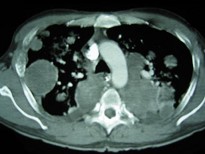

[单选题]男,33岁,咳嗽1周,有骨肉瘤病史,结合CT,最可能的诊断是( )。图1图2A.肺梗死B.粟粒型肺结核C.肺骨肉瘤转移D.结节病E.错构瘤

[单选题]33岁,男,咳嗽1周,有骨肉瘤病史,请结合胸片和CT选出最可能的诊断()A.肺梗死B.粟粒性肺结核C.骨肉瘤转移D.结节病E.错构瘤

[单选题]33岁,男,咳嗽1周,有骨肉瘤病史,请结合胸片和CT图,选出最可能的诊断()A .肺梗死B .粟粒性肺结核C .骨肉瘤转移D .结节病E .错构瘤

[单选题]33岁,男,咳嗽1周,有骨肉瘤病史,请结合胸片和CT选出最可能的诊断A . 肺梗死B . 粟粒性肺结核C . 骨肉瘤转移D . 结节病E . 错构瘤